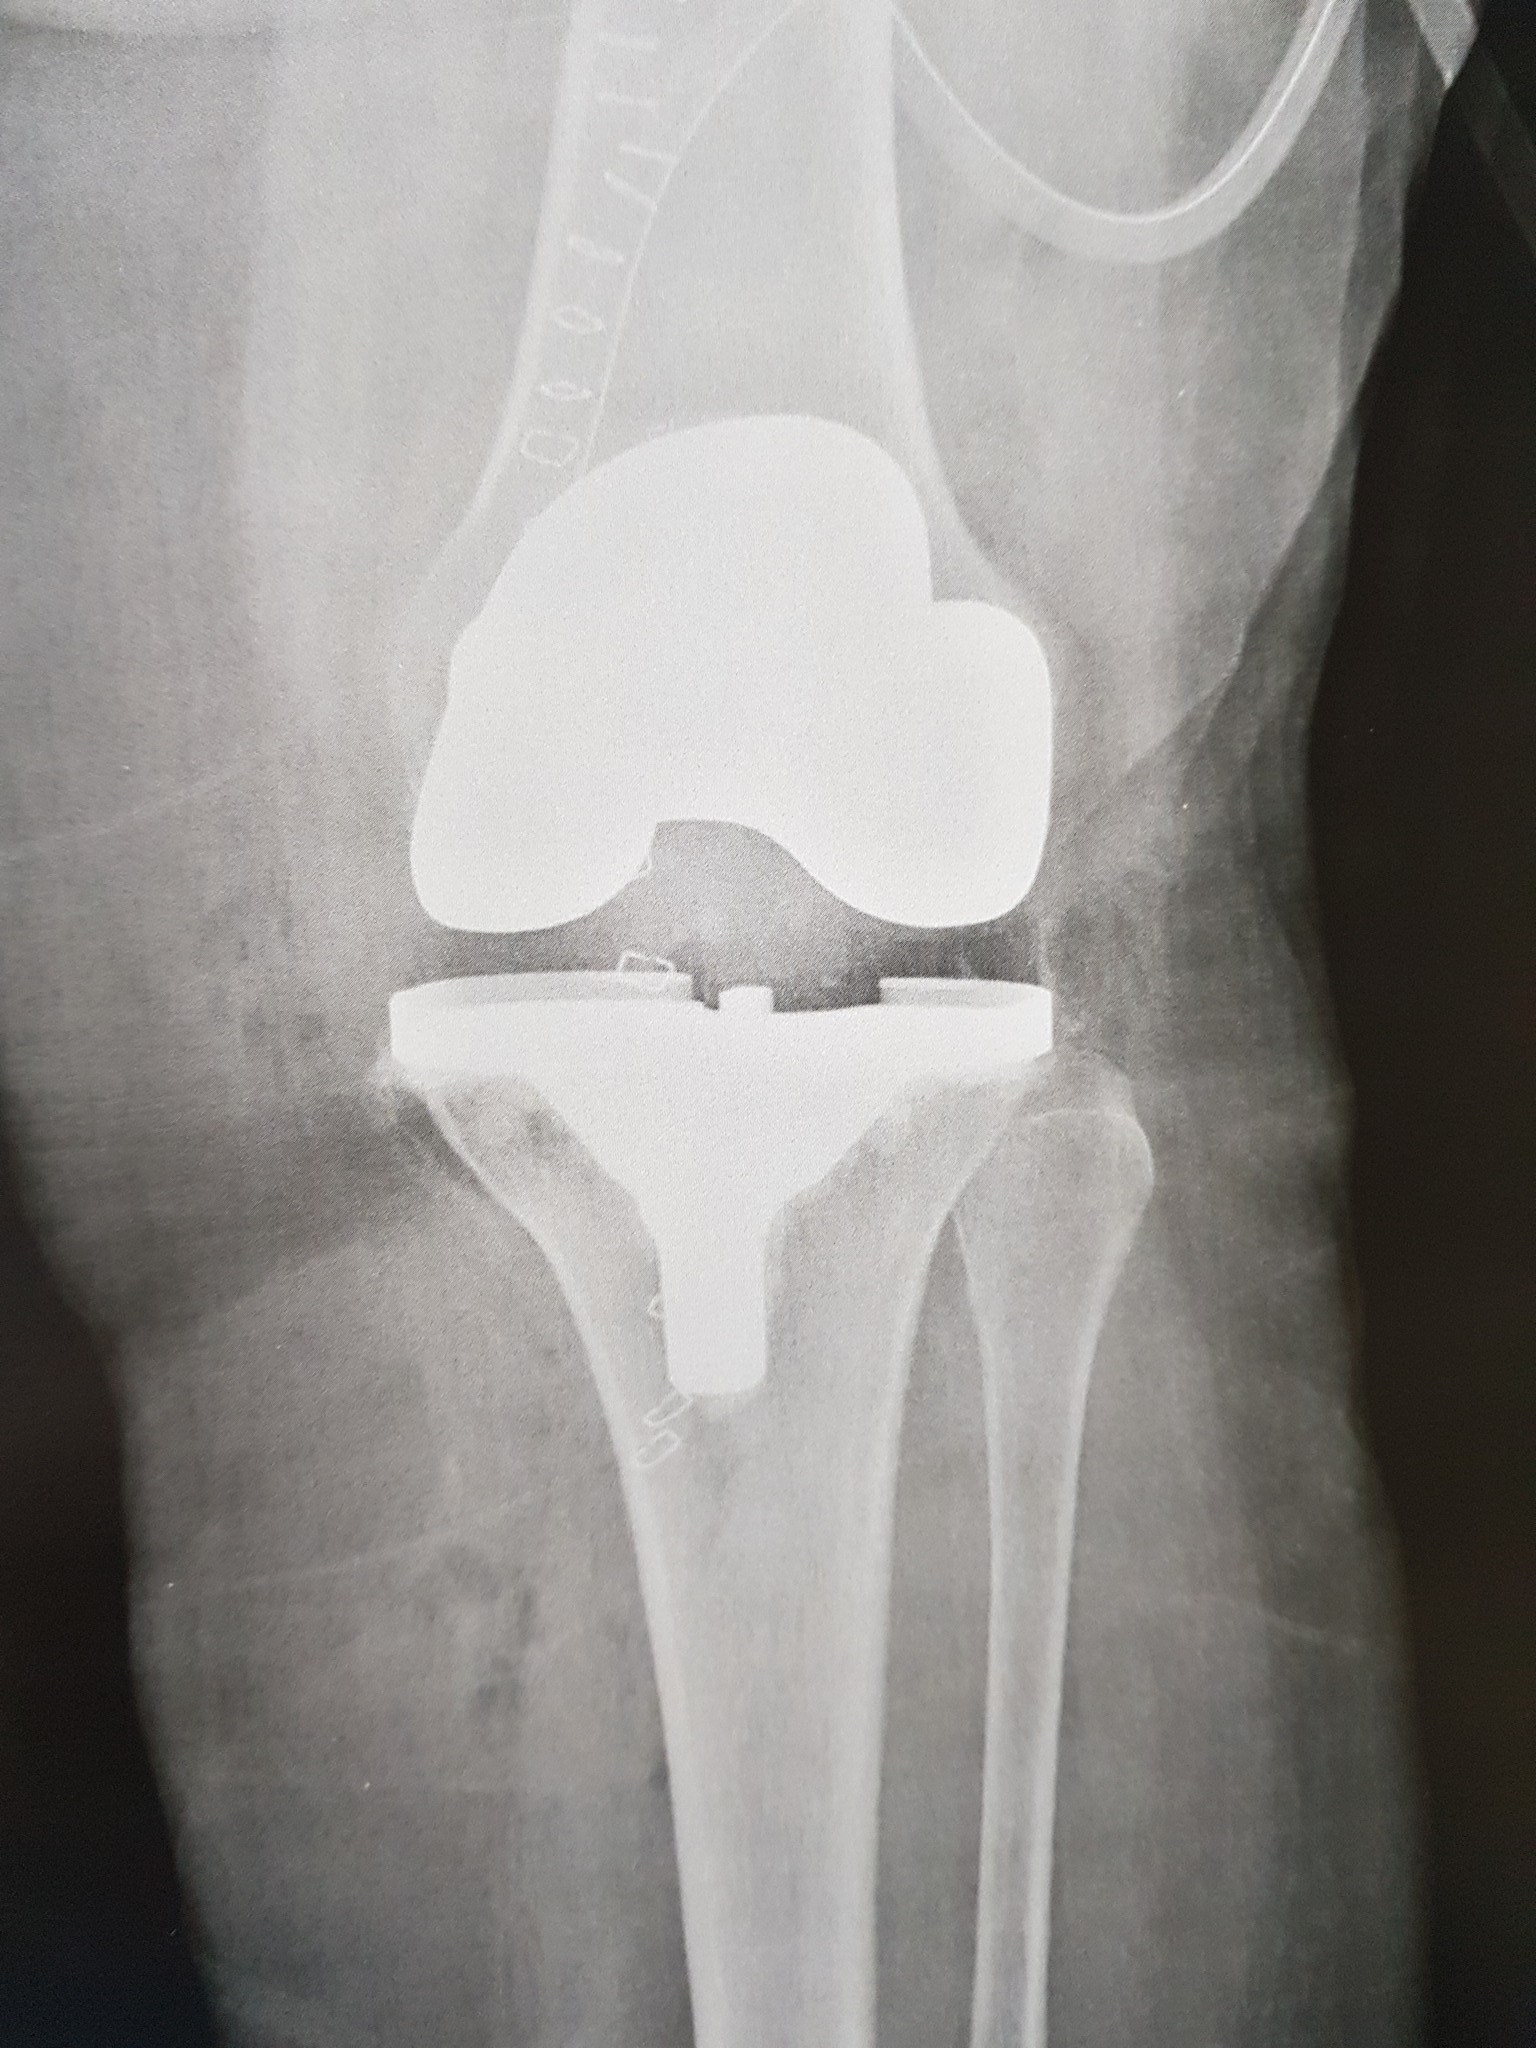

زراعة المفاصل الصناعية ورك و